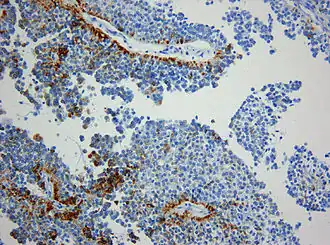

Histologisch handelt es sich um einen neuroektodermalen Tumor, der mit einem papillären Aufbau ein epithel-ähnliches Aussehen hat. Die Tumorzellen sitzen häufig mit breiten Fortsätzen den Blutgefäßen auf, so dass der Eindruck plumper Pseudorosetten entsteht. Auch ependymale Rosetten wie bei Ependymomen können vorkommen. Die mitotische Aktivität der Tumorzellen ist meist moderat. Nekrosen sind häufig und können zur Fehldiagnose eines Plexuskarzinoms verleiten. In der Vergangenheit sind papilläre Tumoren der Pinealisregion häufig auch als Plexuspapillom oder papilläres Ependymom fehlinterpretiert worden. Das immunhistochemische Expressionsprofil (kräftige häufig punktförmige Expression von Zytokeratin) bei meist fehlender Expression des Epithelialen-Membran-Antigens (EMA, in Ependymomen positiv) und des Kaliumkanals Kir7.1 (in Plexuspapillomen und Plexuskarzinomen positiv) erlaubt jedoch in den meisten Fällen eine diagnostische Abgrenzung.[3]